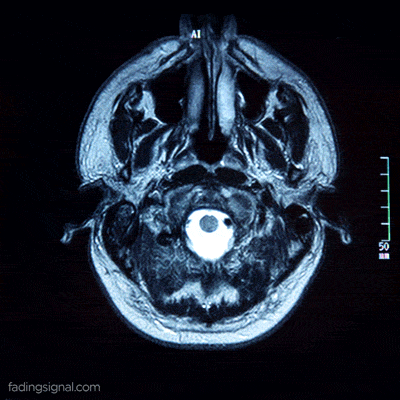

Hjernens kemi har indflydelse på dit humør. Det er en fascinerende men kompleks proces, hvor enhver ubalance eller ændring i vores neurotransmittere kan få os til at opleve alt fra motivation til tristhed til glæde. Så det er vigtigt at forstå det grundlæggende, så du kan håndtere depression.

Depression er også forbundet med bestemte aminosyrer og neurotransmittere som serotonin, norepinephrin og dopamin.